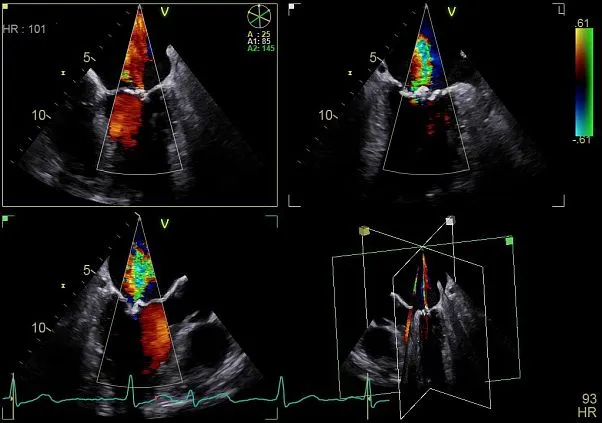

Клинические изображения

- Эхокардиография детей и взрослых

Компактный УЗИ аппарат экспертного класса Vivid S70 с поддержкой объемной чреспищеводной эхокардиографии — 4D TEE, поднимает диагностику заболеваний сердечно-сосудистой системы на новый уровень, позволяя сделать отделения кардиоваскулярной диагностики по-настоящему передовыми и современными.

- Бескомпромиссный уровень качества визуализации как в двухмерном режиме, так и в режиме объемной реконструкции, а также гарантируя высочайшую чувствительность при цветовом картировании кровотока и допплерографии.

Экспертное качество изображений при проведении 2D TTE исследований и при обычной трансторакальной эхокардиографии дает возможность проводить сложные кардиологические исследования и получать достоверные результаты для назначения эффективного лечения.

Благодаря своим техническим возможностям система Vivid S70 позволяет получать достоверные данные для количественной оценки даже при проведении исследований пациентам с избыточным весом или пациентам состояние которых затрудняет проведение диагностики, а технология датчиков XDclear работающая в паре с платформой cSound гарантирует беспрецедентный уровень качества изображений.

Количественный анализ для выбора стратегии лечения

Благодаря пакету простых и интуитивно понятных средств количественного анализа реализованным в ультразвуковой системе Vivid S70 врачи могут быстро и точно оценить уровень поражения сердечно-сосудистой системы и определить стратегию лечения.